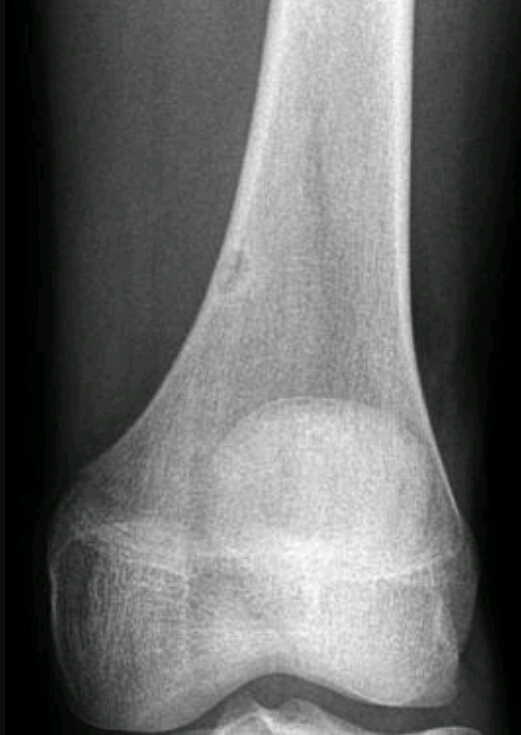

Findings? Diagnosis?

Sunburst periosteal reaction, dense sclerotic lesion at the proximal aspect of the humerus in the metaphyseal region, Codman triangle

Osteosarcoma